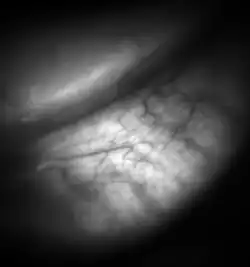

![Meibomian glands in the lower eyelid imaged under amber light to show vasculature support and the gland structure [epiCam].](./_assets_/Meibomian-glands.png)